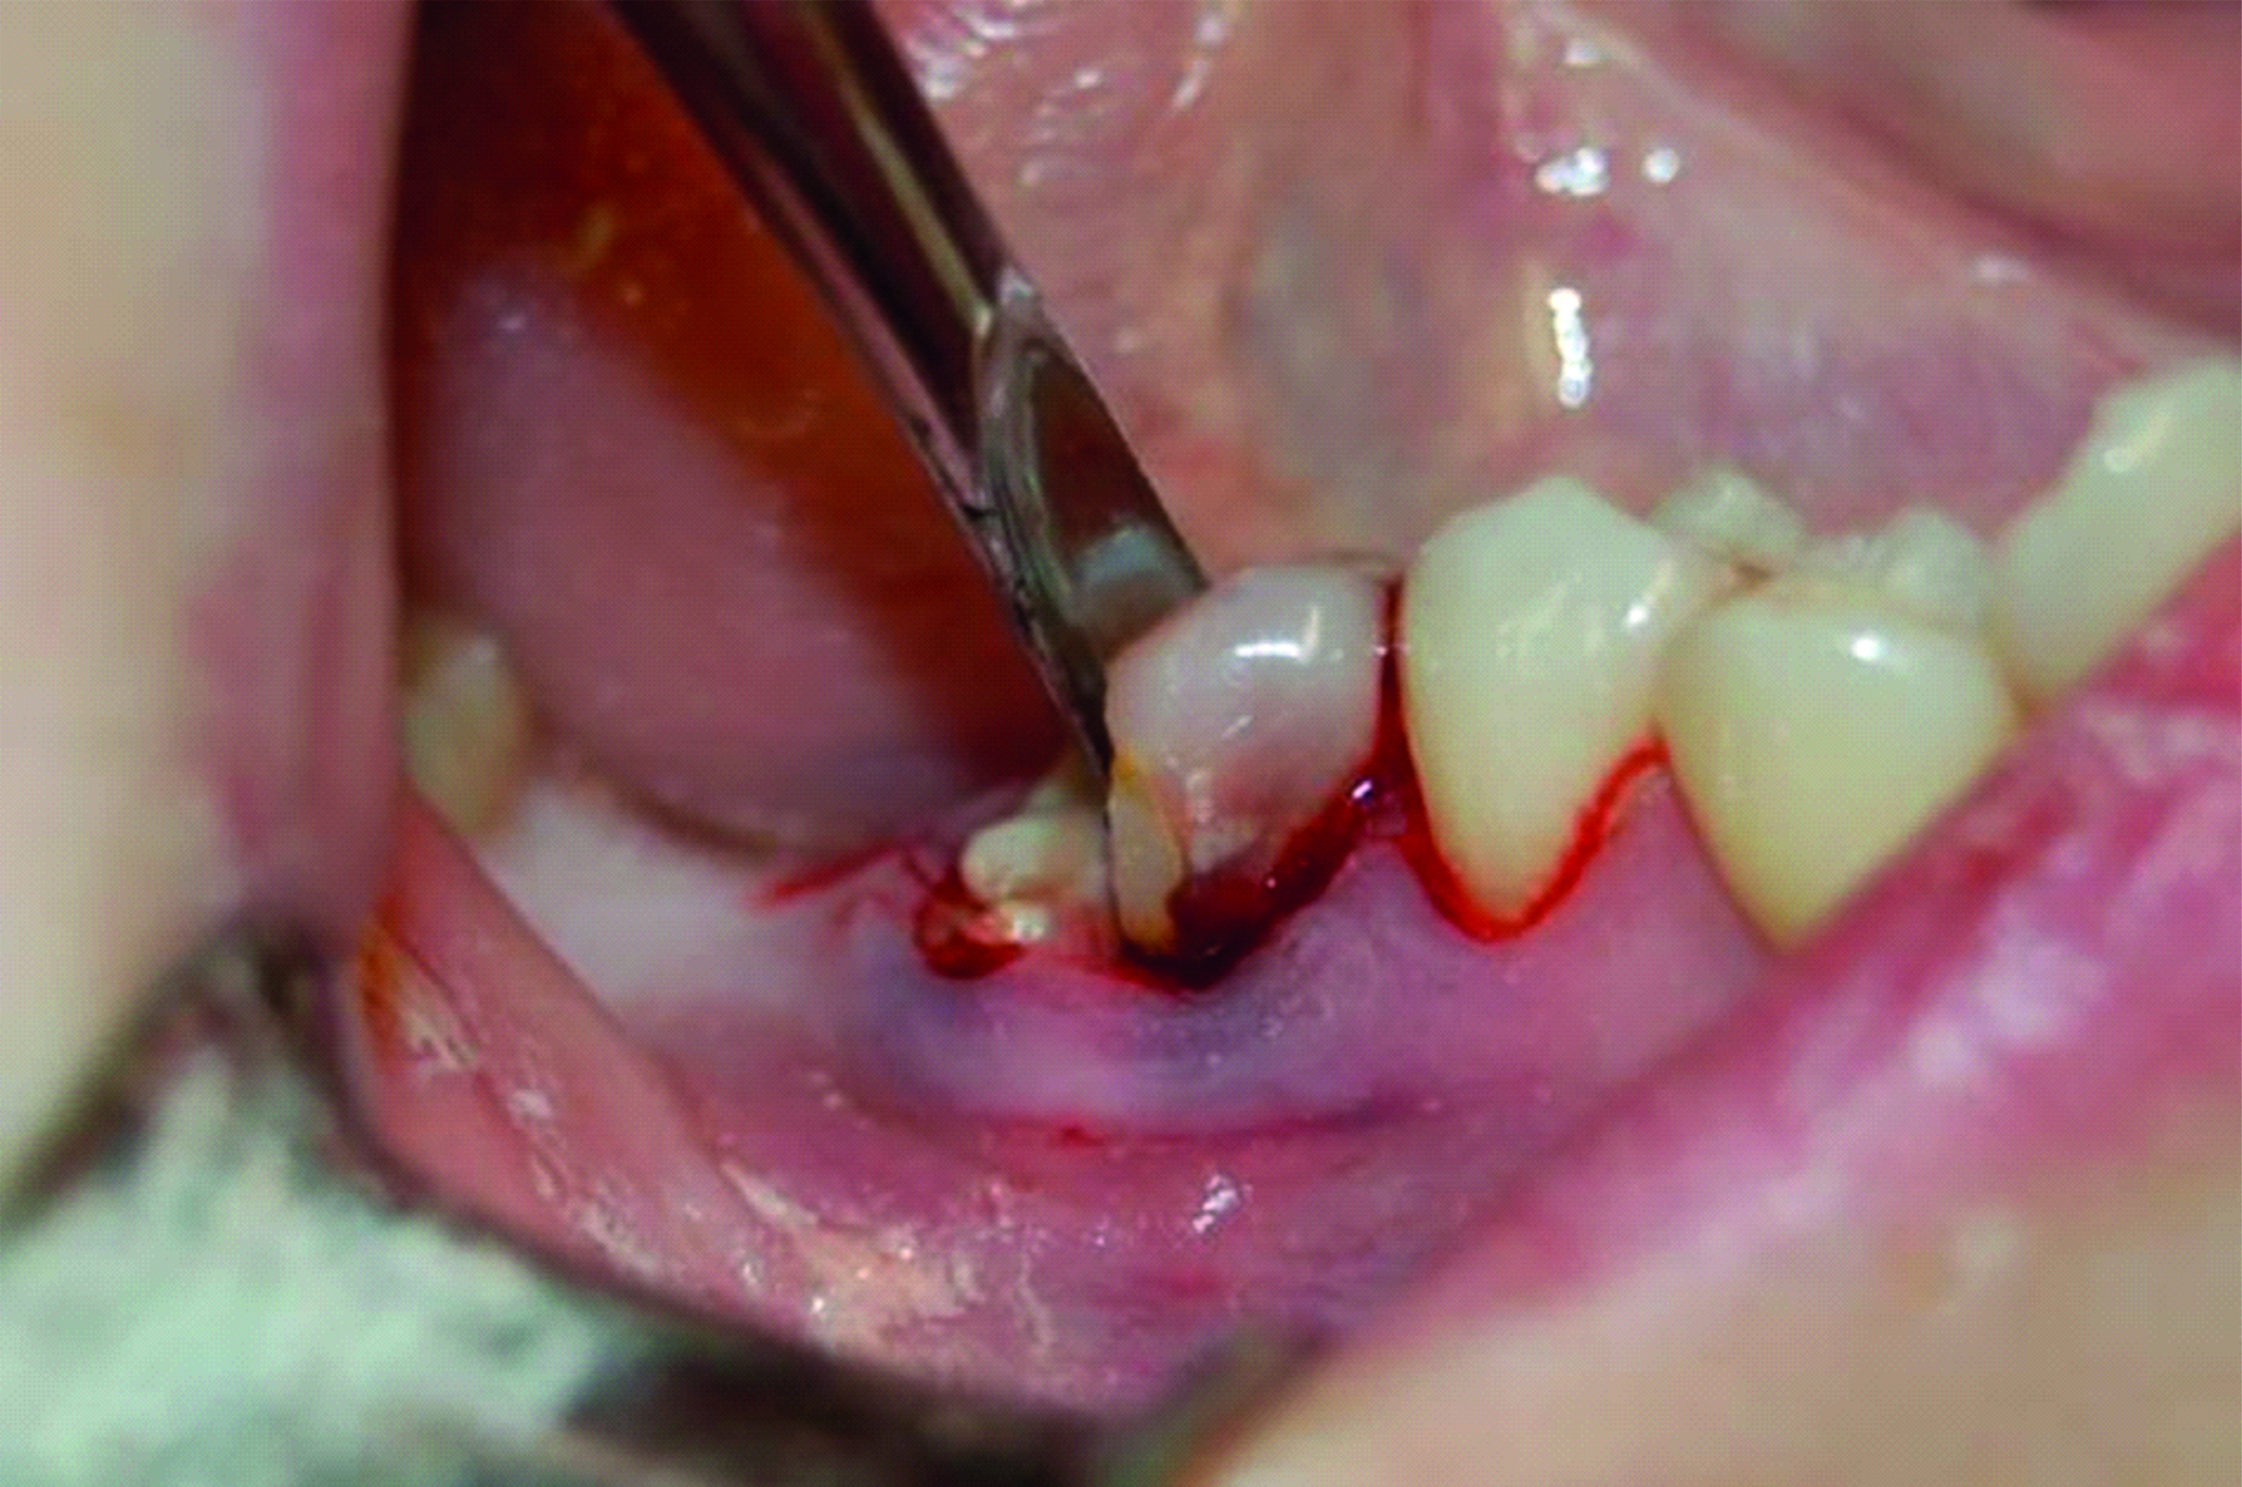

Пациентка К., 36 лет, обратилась в клинику по поводу периодически возникающих болей в зубе 4.6. Зуб ранее лечен с использованием резорцин-формалинового метода. По данным жалобы, анамнеза, осмотра и рентгенографического исследования был поставлен диагноз «хронический гранулирующий периодонтит зуба 4.6». Было принято решение об удалении данного зуба и установке двух имплантатов: в область ранее удаленного зуба 4.7 и одномоментная имплантация в область зуба 4.6. Зуб 4.6 был атравматично удален с использованием прямого наконечника, хирургических боров, элеваторов (рисунок 1).

Рисунок 1. Атравматичное удаление зуба 4.6 с использованием турбинного наконечника, хирургических боров, элеваторов.

Атравматичное удаление позволило сохранить все стенки альвеолы и межкорневую перегородку, что в свою очередь способствовало первичной стабилизации установленного имплантата (рисунки 2, 3).